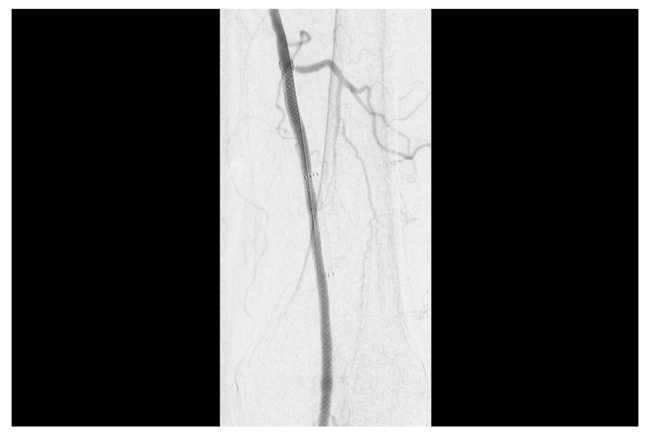

The following is a description of our own technique. Subintimal implantation of a self-expanding interwoven nitinol stent begins with contralateral femoral access. Following diagnostic arteriography, heparinization, and exchanging for a longer sheath, a guidewire is advanced across the occluded segment and stent in the subintimal plane. This is achieved with the use of an angled support catheter in combination with a prolapsed 0.035” wire. Using a prolapsed wire, the wire does not pass through the interstices of the occluded stent. Once across the length of the occluded stent, wire manipulation as well as the use of angled support catheters allow for the redirection of the wire back to the intraluminal space. Re-entry devices could be used to facilitate this; however, we have not found the need to do so. Following this, treatment of distal disease is performed. Once all outflow issues are addressed, the area of occlusion is aggressively pre-dilated with conventional semi-compliant angioplasty balloons (POBA) (Figure 1). The interwoven stent is deployed over a 0.014” wire with care to ensure appropriate cell geometry and minimize any elongation (Figure 2). The stent is not post-dilated after deployment.